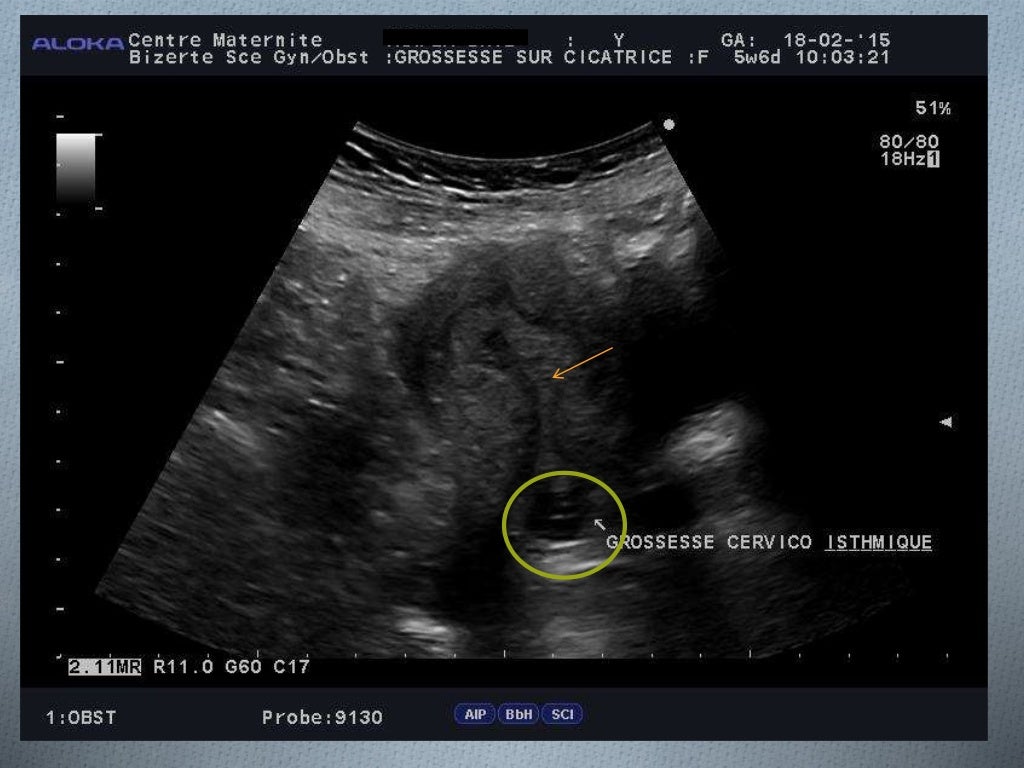

Endométriose pariétale sur cicatrice de césarienne La Revue du Praticien. Une deuxième grossesse après une césarienne soulève des questions légitimes Le chirurgien procède alors à une intervention chirurgicale et réalise une incision horizontale assez basse juste au-dessus de l'os pubien, afin d'extraire le bébé de l'utérus